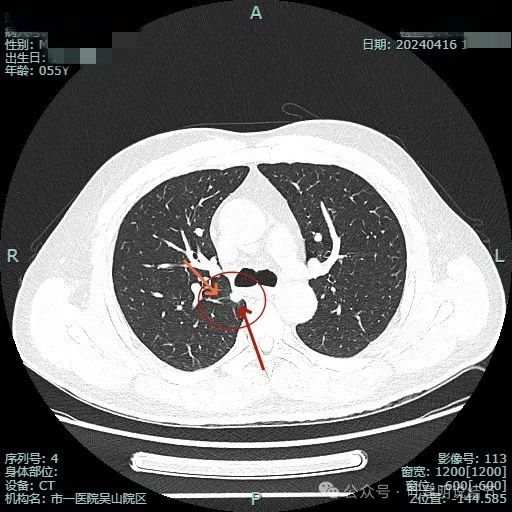

边缘区较淡,也显得有点散。

病灶没有钙化。

纵隔窗可见。